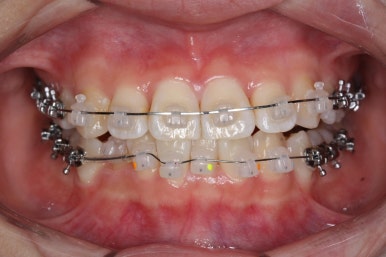

점점 치열이 가지런해지고 있습니다.

이제 치열은 거의 가지런해졌습니다.

치열이 가지런해졌다는 뜻은 이제 곧 뒤로 당기기가 가능해졌다는 뜻이기도 합니다.

우선 윗니가 먼저 가지런해졌기 때문에 윗니부터 뒤로 당기기 시작합니다.